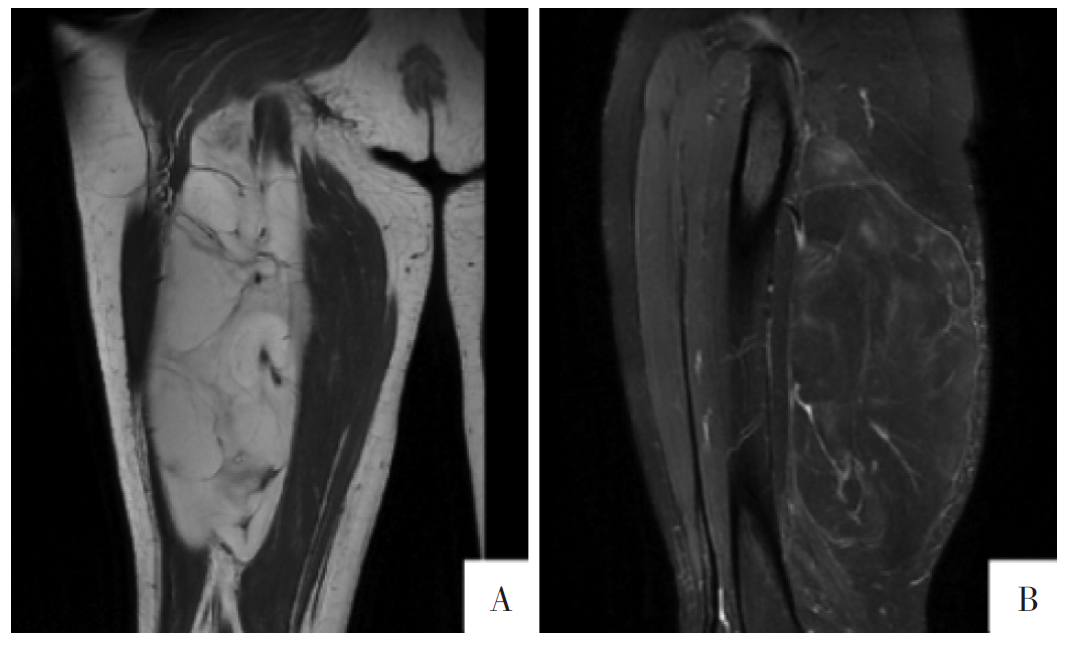

图6

病人女,47岁,右侧大腿软组织ALT/WDLPS。A图,冠状面T

1

WI影像上可见软组织团块状高信号,与皮下脂肪组织信号相近,病灶边缘清楚,内部见低信号分隔影。B图,矢状面T

WI-FS影像上显示病灶内高信号明显减低。